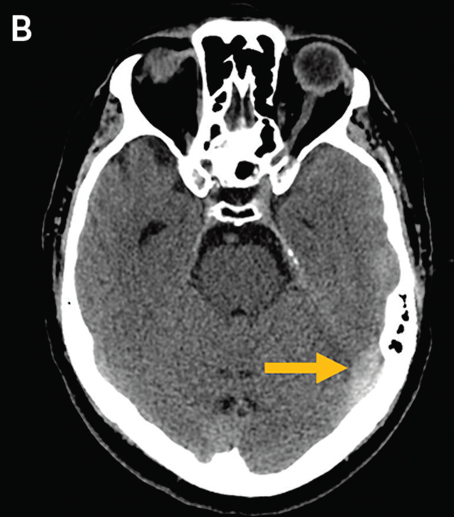

A 50 yo man presented to the ED with acute onset aphasia. He is not able to report a history, but BP Is 215/95.

Non-contrast HCT reveals this bleed…

What do you want to see next? Image

A cord sign! A hyperdense signal within a venous sinus (in this case transverse / sigmoid sinus) Image